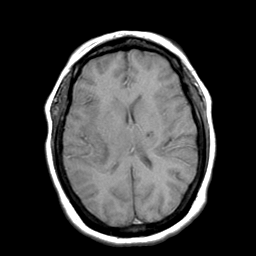

Cerebral hemorrhage, MR Study mr-t1 -- Slice #14

[Home][Help][Clinical] Slice 14